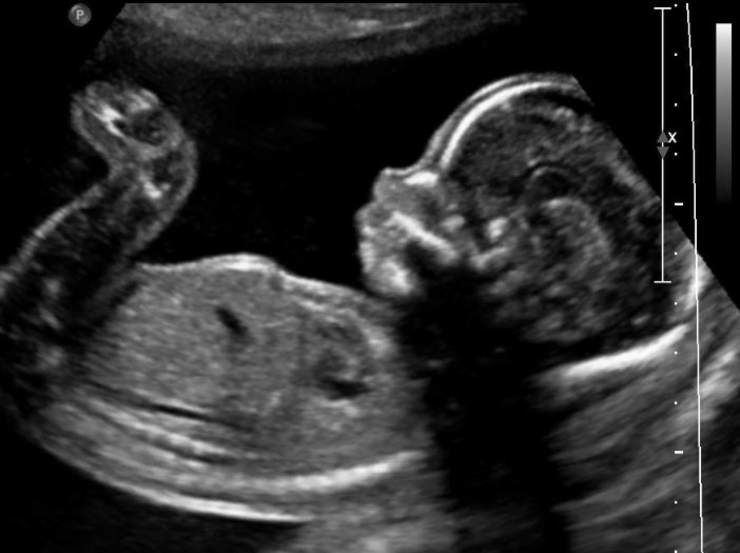

L-ewwelnett, biex it-tfal inressquhom lejn Ġesù rridu nħalluhom jgħixu. Għalhekk jiena nitlob il-barka fuq il-gżejjer tagħna, li aħna nibqgħu ngħożżu l-ħajja sa’ mill-bidu tal-konċepiment tat-tarbija fil-ġuf. Anke jekk tarbija ma tkunx fil-ġuf! Tarbija konċeputa, anke fil-laboratorju, anke permezz tal-prattika tal-IVF, hija ħlejqa u għandha d-dinjità tagħha. Dak li aħna nseħjulu embrijun huwa aħna meta kellna ftit siegħat jew ftit jiem. Jien kont embrijun, Eċċellenza (President ta’ Malta) int ukoll kont embrijun, ilkoll kemm aħna konna embrijuni. Meta nitkellmu fuq l-embrijuni, biex nifhmu x’irridu nagħmlu ejjew ngħidu: jiena kieku kelli leħen kont ngħidilhom ‘iva tistgħu tiffriżawni għax għandkom bżonni ħamsin sena oħra? Jew inkella tistgħu tqattgħuni biċċiet għax għandkom bżonni għar-riċerka?’

Mela ejjew nitolbu lill-Mulej jagħtina dawl biex nifhmu x’aħna ngħidu meta nużaw il-kelma embrijun. L-embrijun huwa t-tarbija li se titwieled disa’ xhur oħra, li se tkun ċittadin, u meta l-Mulej jgħidilna “ilqgħu lit-tfal” mhux qed jgħidilna biss it-tfal li twieldu, qed jgħidilna biex nilqgħu liċ-ċkejnin tagħna u nibqgħu nipproteġuhom, biex nipproteġu d-dinjità tagħhom.